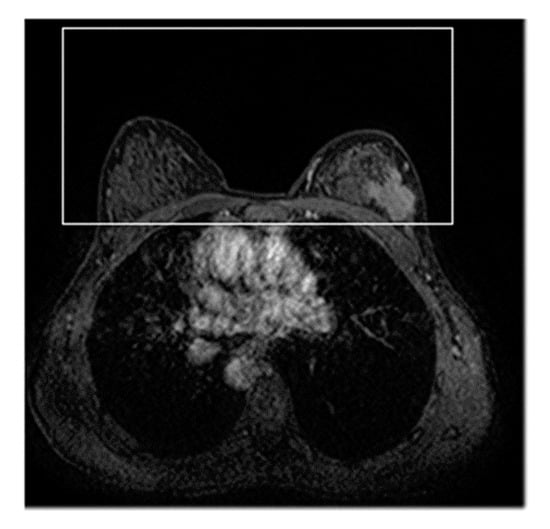

2.1. ROI Hunter Procedure